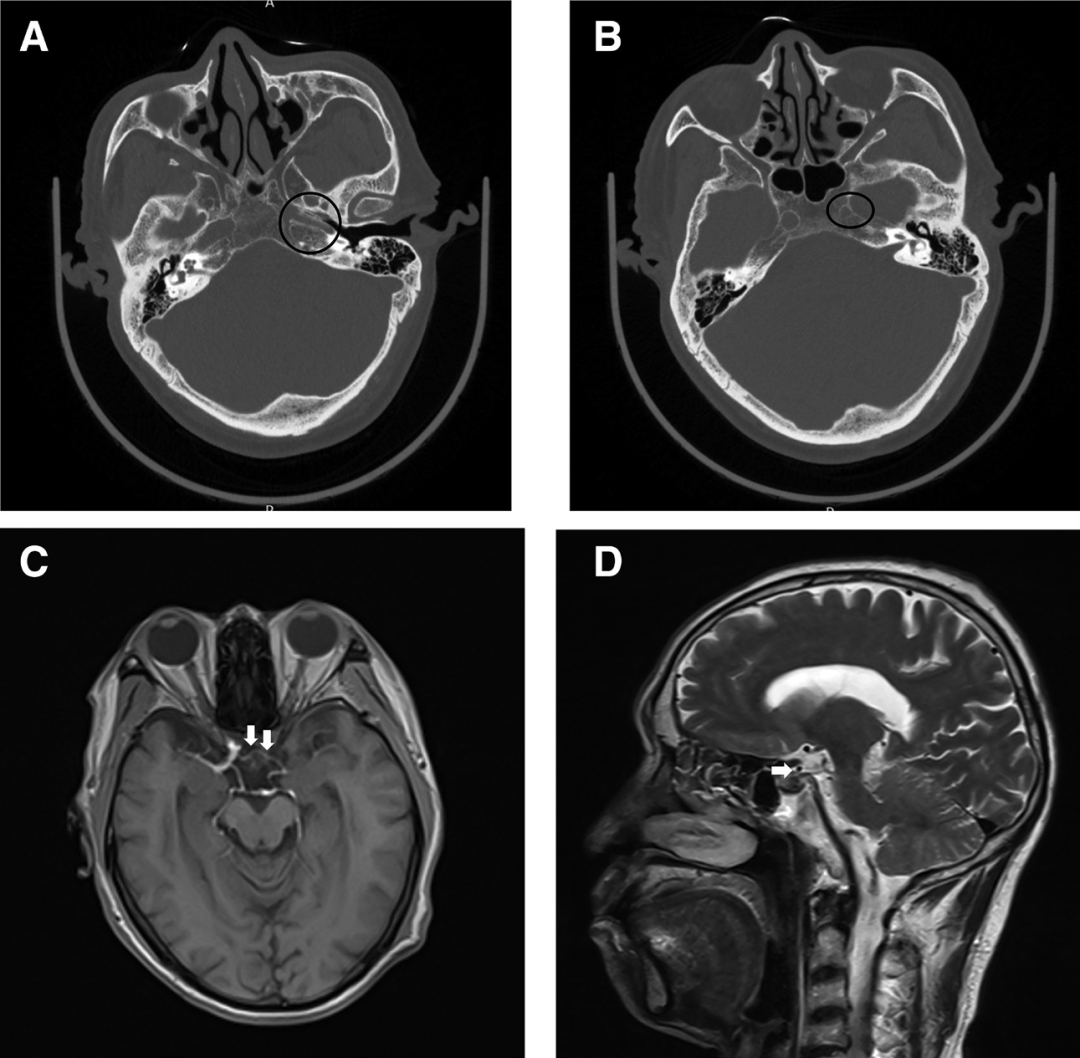

1个月前诊断为无症状的右颈内动脉(ICA)严重狭窄,并入院接受右颈动脉内膜切除术。手术前检查显示永存原始上颌动脉和左侧ICAD型发育不良(图1)。

图1.A和B,颅底薄层扫描CT显示,左侧骨性颈动脉管内径(黑圈)明显小于右侧,提示左侧颈内动脉D型发育不良。轴位T1加权(C)和矢状T2加权(D)图像显示鞍底永存原始上颌动脉(箭头)